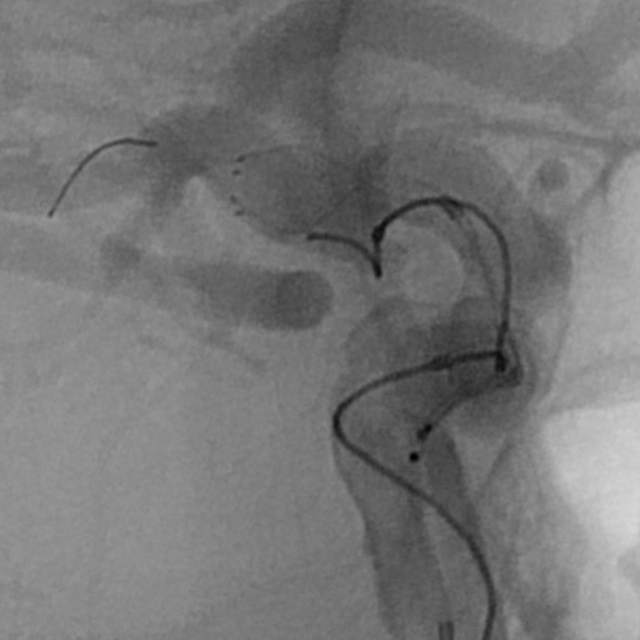

病情变化:中年男性患者,由于头晕查体发现后交通动脉瘤,第一次造影可见形态尚规则,患者及家属经过反反复复的思想斗争,决定采用外科干预。3天后,术中发现动脉瘤的形态已经出现改变,瘤囊的远端出现子瘤。

术中评估:动脉瘤位于后交通段的位置,靠近颈内动脉分叉部,颈内动脉交通段的长度相对短小,而且呈现喇叭口的形态,支架不容易锚定,容易出现跳跃“”嗑瓜子”现象。如果支架超过分叉部,覆盖大脑前动脉的起始部,可能会造成后续的大脑前动脉的血管变细。

手术难点:支架远端超过分叉部,操作简单;支架远端若紧邻分叉部近段,操做要求高。

手术过程:术中采用“一个支架+一个弹簧圈”的简约模式顺利结束手术,消除了动脉瘤破裂出血的风险。